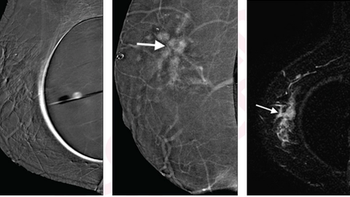

Images can detect non-mass enhancement extension that correlates to tumor involvement of the nipple.

Images can pinpoint which women are at risk for ischemia and nipple necrosis.